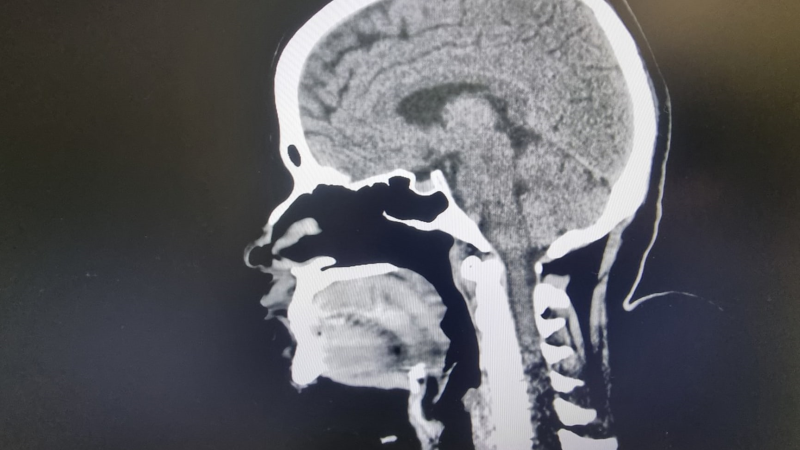

Začalo to pícháním pod žebry. Nikola Hezucká popsala začátek manželovy nemoci

Manželka zesnulého Patrika Hezuckého (†55) dala sledujícím na Instagramu prostor pro laskavé otázky, aby ukojila jejich zvědavost ohledně manželovy nemoci a jeho odchodu. Promluvila o...